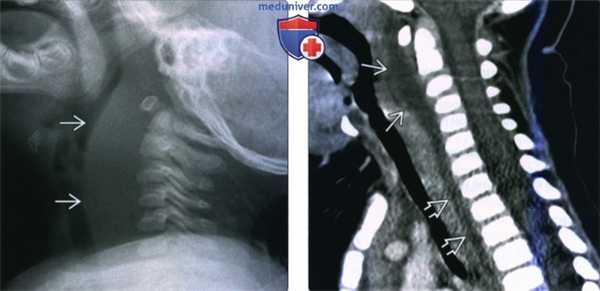

(Слева) Рентгенограмма в боковой проекции, 12-месячный ребенок с сепсисом. Отмечается значительное утолщение предпозвоночных мягких тканей.

(Справа) КТ с КУ, сагиттальная реконструкция, этот же пациент. Четко выявлена причина утолщения предпозвоночных тканей - крупный заглоточный абсцесс с выпуклой передней поверхностью. Жидкостное содержимое распространяется в заднее средостение.

(Слева) Рентгенограмма в боковой проекции, ребенок трех лет, шея находится в нейтральном положении. Определяется выбухание предпозвоночных мягких тканей. Как можно понять по куполу легкого, снимок сделан на выдохе.

(Справа) Этот же ребенок, рентгеноскопия в боковой проекции. Снимок сделан во время глубокого вдоха. Видно, что толщина предпозвоночных тканей в норме.